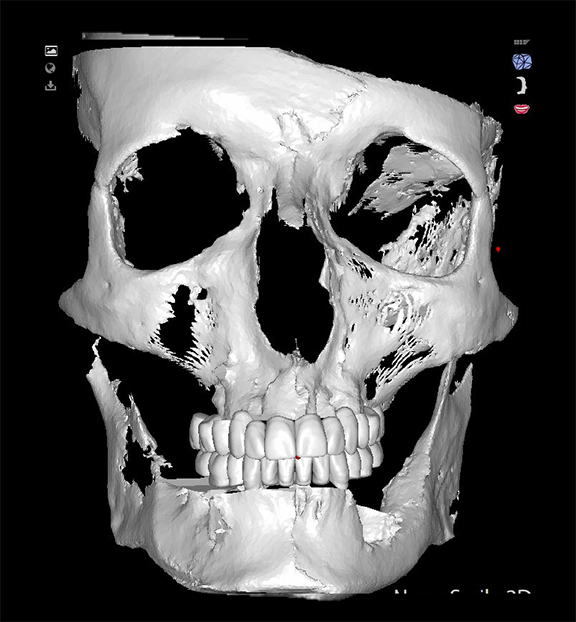

In a more complicated case, often there are more complicated starting points. The patient shown in Figure 8 had bite posture problems, caries, periodontal disease, failing restorations and implants, and a history of head-and-neck cancer. Such a patient may logically fear the unknowns of treatment, but with the treatment planning and rendering capabilities robotics provide, the practitioner could determine exactly what the patient needed, convey the information to the patient, and deliver promised results.

Fig 8. The patient had bite posture problems, caries, periodontal disease, failing restorations and implants, and a history of head-and-neck cancer.

Figure 8